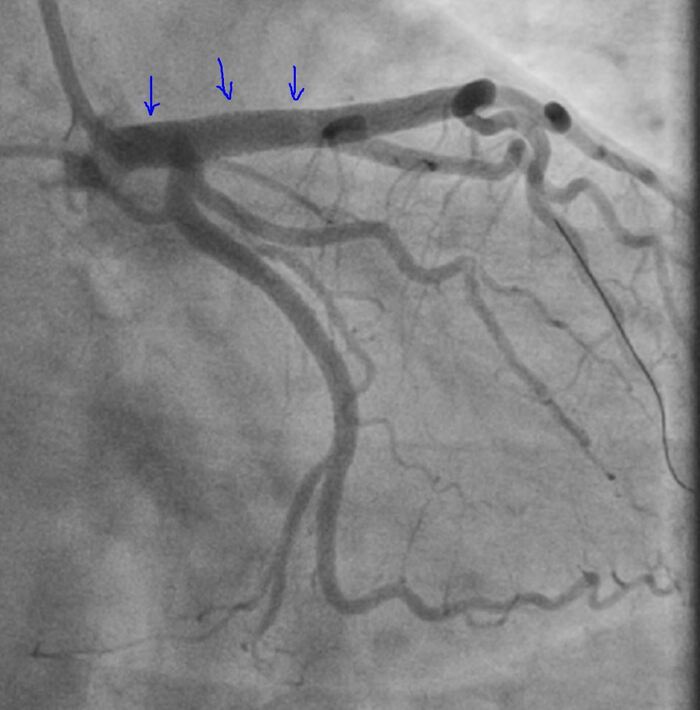

Итак на коронарографии такая картина при первой же съемке:

Стенозирование передней межжелудочковой артерии (ПМЖА) в начальном (проксимальном сегменте), инфаркты при полном закрытии ПМЖА в этом сегменте часто фатальные, либо приводят к инвалидизации

Оператор, с учетом такой картины, решает уточнить морфологию поражения, для выбора правильной тактики лечения (то что это нужно стентировать сомнений нет).